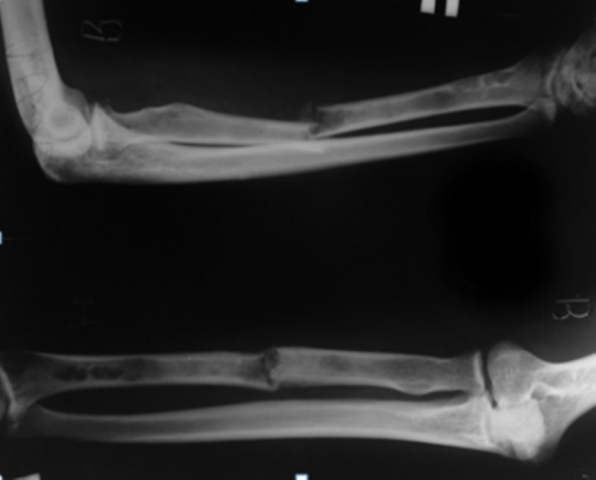

Лучевой называется кость в составе предплечья руки . Она начинается у локтя и продолжается до запястья . Нижняя ее часть, которая Виды повреждений . Классификация переломов лучевой кости довольно обширная . Они бывают закрытые и открытые, патологические и . . .

Лучевая кость - это парная кость в составе предплечья, которая на пару с локтевой костью участвует в образовании двух суставов: локтевого и Если после травмы у вас есть подозрение на перелом, то вам необходимо обратиться в травмпункт . Там вам сделают рентген и в случае . . .